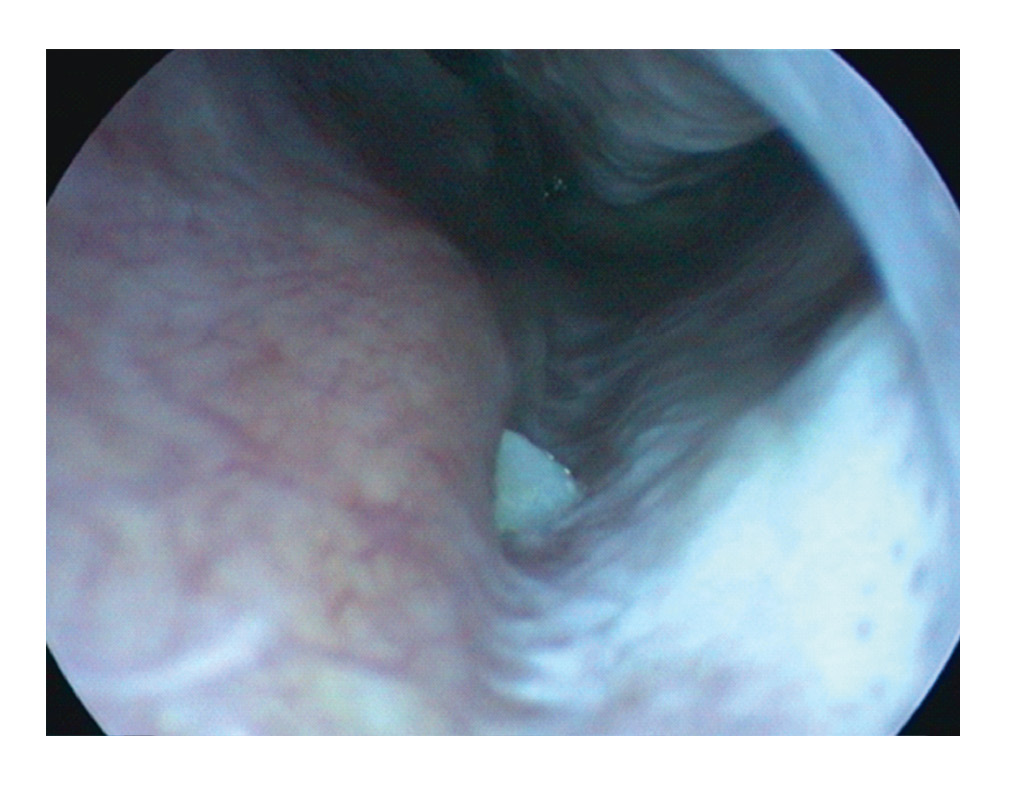

При осмотре полости рта: на верхней челюсти патологических изменений не выявлено. На компьютерной томограмме полости носа и околоносовых пазух (рисунки 2, 3) данных за патологию околоносовых пазух не выявлено, перегородка носа по средней линии, в альвеолярном отростке слева с переходом на дно полости носа отмечается ромбовидной формы образование костной плотности размером 3,6*2,7*8,5, костный канал не определяется (соответствует зубу).

Рисунки 2, 3. КЛКТ полости носа и околоносовых пазух, корональная и аксиальная проекции. / Figures 2, 3. CBCT scan of the nasal cavity and paranasal sinuses, coronal and axial projections.